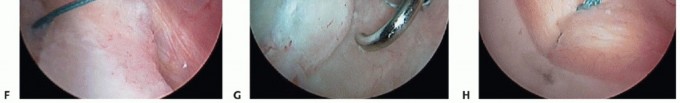

TECH FIG 1 • A. Probe entering the posterior cannula is demonstrating mobility of posterior Bankart lesion with evidence of granulation tissue in the defect. B. After the lesion is defined, a Liberator knife is introduced to take down the fibrous interface in the posterior Bankart lesion. C. After preparation using a high-speed burr, the posterior inferior aspect of the glenoid is lightly decorticated in preparation for anchor placement. D. Initial anchor placement begins at the inferior extent of the glenoid with the use of a guide. E. First anchor in place 2 mm up on the articular surface.

TECH FIG 2 • A. The Spectrum suture passer is used to capture inferior capsular tissue and the posterior band of the IGHL. B. After anchor placement, stability is assessed with gentle traction on the anchor sutures and a monofilament suture is passed through the suture passer. (continued)

TECH FIG 2 • (continued) C. The monofilament suture, having been passed through a capsule inferiorly, is drawn up to assess capsular mobility and determine the amount of translation. D. One limb of the anchor suture is tied to the monofilament suture, which is then drawn back out the posterior cannula, thus creating a simple stitch. E. Having tied the suture on the first anchor, a drill hole is created 7 to 8 mm superiorly for the second anchor. F. A second anchor suture has been passed, demonstrating the purchase of additional posterior capsule. G. With the final superior anchor in position, the suture passer is directed superiorly to capture additional posteromedial capsule and superior labrum. H. Final anchor sutures are tied, demonstrating excellent reconstruction of the posterolabral defect, recreating the posterior labrum bumper effect.